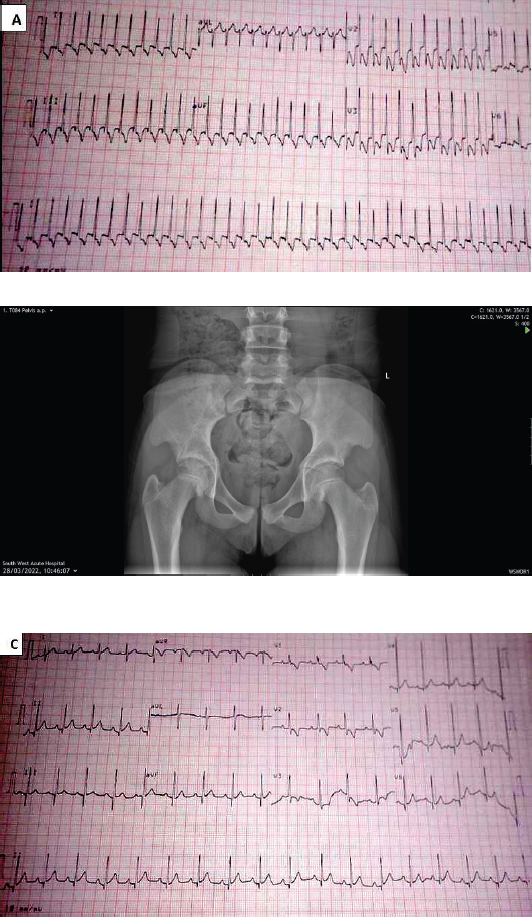

A 3-month-old male presented with a history of low-grade intermittent fever and fast breathing of 1 day duration. Fast breathing progressively worsened and was not associated with cough, catarrh, cyanosis, excessive sweating or prolonged feeding time. He had episodes of inconsolable cries. On examination, he was irritable in respiratory distress, afebrile, not cyanosed and oxygen saturation in room air was 83%–91%. The heart rate was 150 bpm, and no murmur was heard. The respiratory rate was 52 cpm with vesicular breath sounds. A diagnosis of possibly acute bronchiolitis was made. He was admitted and commenced on intranasal oxygen. The chest radiograph was normal. He had hypokalaemia which was corrected. On further review, he was noticed to have desaturated despite being on 100% oxygen. He became lethargic, sweating profusely with his heart rate ranging between 295 and 300 bpm. An urgent electrocardiograph revealed SVT (Figure 1A) and echocardiography showed a structurally normal heart. There was no response to vagal manoeuvre. He was transferred to the intensive care unit. Systolic blood pressure recordings were in the hypotensive range between 60 and 65 mmHg while the diastolic was not recordable. His pulses were small volume, barely palpable with cold clammy extremities. A diagnosis of cardiogenic shock secondary to a SVT was made. Intravenous fluid with a plasma expander was administered to correct the shock. He was on nil per oris, continuous positive airway pressure and a urethral catheter to monitor urine output. A cardiologist reviewed and commenced him on oral propranolol initially with slight improvement. He later developed SVT with aberrancy (Figure 1B) for which intravenous amiodarone was given and subsequently changed to oral amiodarone. Vital signs were monitored and subsequently became normal. Feeds were recommenced via cup and spoon. Repeat electrocardiography showed sinus rhythm as shown in Figure 1C. He was discharged home on oral propranolol. Parents were educated on how to monitor oxygen saturation and vital signs at home. He had several episodes of SVT following febrile illnesses after the first episode of arrhythmia. He was recommenced on oral amiodarone, digoxin and propranolol. Their parents were counselled on the management of fever and he was weaned off amiodarone. He is currently being followed up and on low-dose propranolol and digoxin. The last episode of SVT was about 3 months ago. Growth and development have been normal. He is currently 2 years of age.

Figure 1. (A) SVT in Case 4. (B) SVT with aberrancy and (C) sinus rhythm in the 3-month-old child after the first episode of SVT.